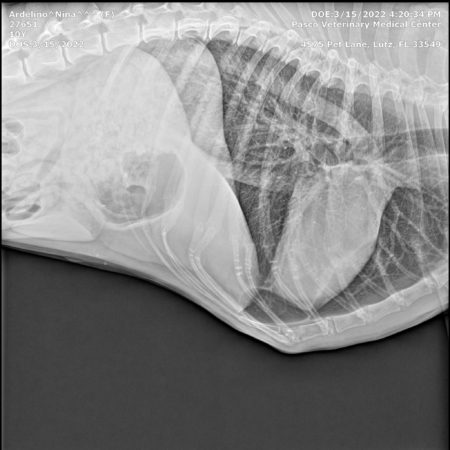

Here are Nina’s X-rays, showing no metastasis, no spread of cancer 22 months post diagnosis of osteosarcoma in dogs:

The results were what we’d hoped for! No Metastasis! Once again there was NO SPREAD of cancer anywhere else in her body.

The tumor had grown to the size of a grapefruit, and was cutting off circulation to her foot. It had also started to seep fluids, through a small sore on the surface of the growth. This meant that we would once again run all the diagnostic tests again to see if, after 22 months, the cancer had metastasized.